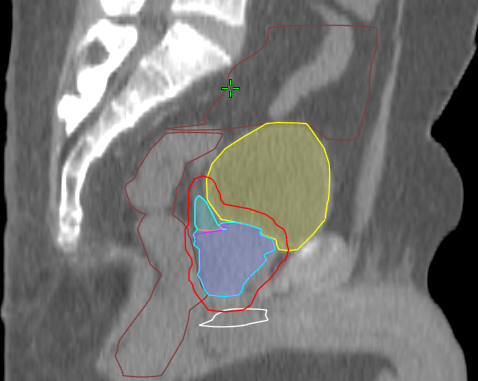

Planning Activities

Prostate Case – Contouring

Prostate Case – Planning